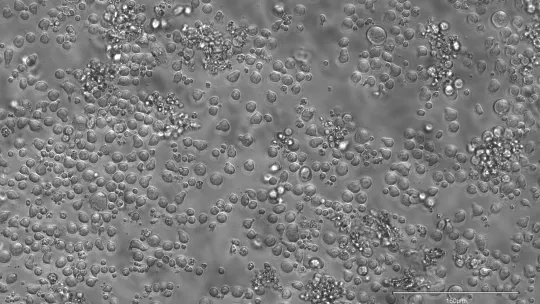

En los jóvenes, hay entre 50.000 y 200.000 células madre sanguíneas activas que producen de 100 a 200 mil millones de células nuevas cada día. Rastrear cada célula sanguínea hasta su célula madre original hasta ahora ha sido solo posible en modelos animales para los que hay que modificar genéticamente el ADN, algo inviable y poco ético en humanos.

El equipo recurrió a las epimutaciones: cambios en las marcas químicas (metilaciones) que se adhieren al ADN y le indican a la célula qué genes activar o silenciar. Cuando una célula madre se divide, estas marcas se copian en las células hijas, dejando un “código de barras” permanente que los investigadores pueden leer para reconstruir el árbol genealógico celular.

Para hacer frente a este reto, los investigadores han desarrollado una técnica llamada EPI-Clone, que lee estos códigos de barras de metilación en cada célula basándose en la plataforma Tapestri de Mission Bio para secuenciación de células individuales. Con ella reconstruyeron la historia de la producción sanguínea en ratones y humanos, identificando qué células madre contribuyen a la sangre y cuáles van abandonando la carrera a lo largo del tiempo.

En la sangre joven, miles de células madre diferentes contribuyen a un conjunto rico y diverso de glóbulos rojos, glóbulos blancos y plaquetas. Sin embargo, EPI-Clone reveló que en ratones de edad avanzada, hasta el 70% de las células madre sanguíneas pertenecían a sólo unas pocas docenas de grandes clones.